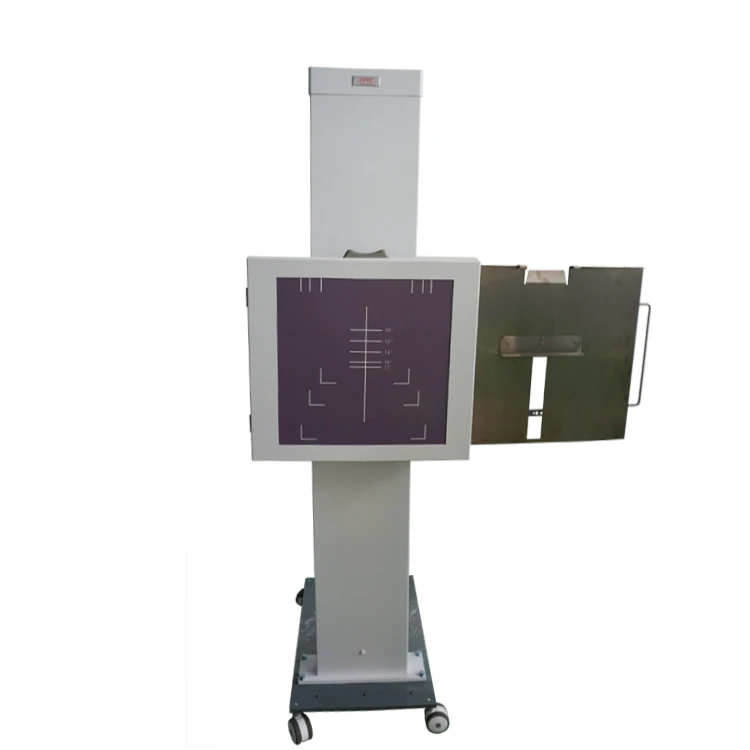

Организация рабочего пространства: стенды для рентгеновских снимков